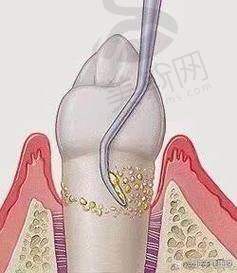

5. 牙周病诊疗中 心:针对牙龈炎、牙周炎开展龈上洁治、龈下刮治、牙周翻瓣术、引导性组织再生术(GTR),采用激光牙周治疗技术,减少出血与疼痛,缩短愈合周期30%。

赵刚 牙周科主事:原黑龙江省医院牙周科主治医师,擅长重度牙周炎系统治疗,开展激光牙周治疗超1000例,引进“牙周组织再生膜技术”,使牙周袋深度减少量提升40%,主编《临床牙周病诊疗图谱》实用手册。

13. 哈尔滨优诺博士口腔龈下刮治(单象限):680元